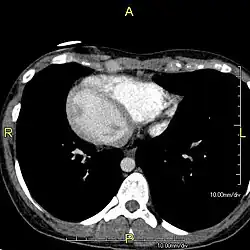

| Situs inversus causes the positions of the heart and lungs to be mirrored. | |

Situs inversus is found in about 0.01% of the population, or about 1 person in 10,000. In the most common situation, situs inversus totalis, it involves complete transposition (right to left reversal) of all of the viscera. The heart is not in its usual position in the left chest, but is on the right, a condition known as dextrocardia (lit. 'right-hearted'). Because the relationship between the organs is not changed, most people with situs inversus have no associated medical symptoms or complications.[1]

The condition affects all major structures within the thorax and abdomen. Generally, the organs are simply transposed through the sagittal plane. The heart is located on the right side of the thorax, the stomach and spleen on the right side of the abdomen and the liver and gall bladder on the left side. The heart's normal right atrium occurs on the left, and the left atrium is on the right. The lung anatomy is reversed and the left lung has three lobes while the right lung has two lobes. The intestines and other internal structures are also reversed from the normal, and the blood vessels, nerves, and lymphatics are also transposed.

If the heart is swapped to the right side of the thorax, it is known as "situs inversus with dextrocardia" or "situs inversus totalis". If the heart remains on the normal left side of the thorax, a much rarer condition (1 in 2,000,000 of the general population), it is known as "situs inversus with levocardia" or "situs inversus incompletus".

Diagnosis of situs inversus can be made using imaging techniques such as x-ray, ultrasound, CT scan, and magnetic resonance imaging (MRI).[9]